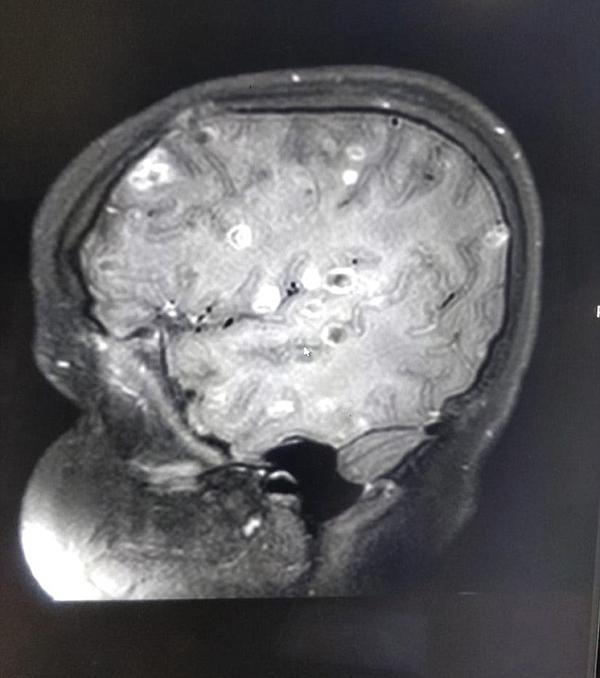

Sau 6 tháng chữa trị mà không có chuyển biến, cha mẹ cô bé rất lo lắng nên đã đưa cô đến Bệnh viện Fortis ở Gurgaon. Sau khi chụp chiếu và kiểm tra kỹ lượng, các bác sĩ rất bất ngờ khi phát hiện có đến trăm quả trứng sán dây đang "yên vị" trong não của cô bé. Đó chính là nguyên nhân khiến em có dấu hiệu bị loạn thần kinh và co giật.

Praveen Gupta, giám đốc thần kinh tại Bệnh viện Fortis, cho biết: “Việc chụp cắt lớp não của cô bé đã thấy hơn 100 chấm trắng hình thành do trứng của sán dây. Nguyên nhân là do ăn phải thực phẩm có chứa trứng sán.

Não là vị trí hay gặp nhất của ấu trùng sán lợn: 60 - 90%, mắt chiếm tỷ lệ: 1 - 3% các trường hợp bệnh. Triệu chứng hay gặp: nhức đầu, chóng mặt, buồn nôn, giảm trí nhớ; nặng hơn có thể rối loạn tâm thần, liệt mặt, liệt tứ chi, nói ngọng, mờ mắt, viêm màng não mạn tính, sút cân, động kinh … và có thể dẫn đến tử vong.